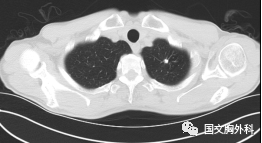

這個(gè)病人檢查胸部CT如圖3:根據(jù)影像學(xué)考慮是惡性腫瘤,行手術(shù)治療后病理回報(bào):“肺膿腫,合并炎癥纖維組織增生”,因此“肺占位”不代表就是惡性腫瘤,診斷金標(biāo)準(zhǔn)是病理診斷。如果檢查后發(fā)現(xiàn)“肺占位”先不要驚慌,及時(shí)就診請(qǐng)??漆t(yī)生會(huì)診指導(dǎo)治療才是關(guān)鍵。